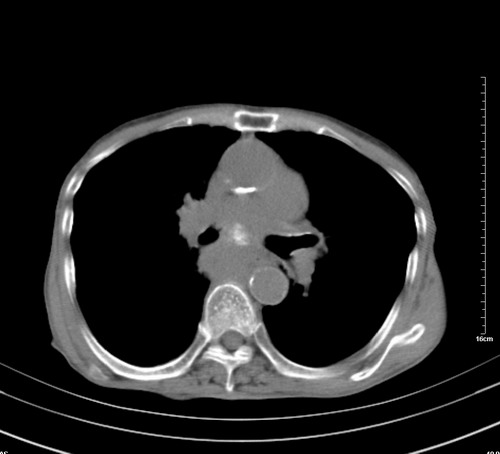

病人,女,79岁,主要因腹疼二月入院,彩超,肝,胆,脾,未见异常,胸透上消化道造影未见异常,化验白细胞增高,内科医生让做胸部ct检查,因为熟人多做了腹部(外科会诊考虑胆囊炎).现ct片如下请假各位战友.

中后纵隔占位,气管、食道受压、变形、移位。恶性可能性大。

1 气管旁、隆突下淋巴结明显肿大,肝左叶外侧段低密影,都考虑转移。

肺癌,纵隔淋巴结转移,肝左叶病变考虑为转移病灶。

后中纵隔团块影,伴气管、食道受压移位,首先考虑转移瘤,肝s5段低密度灶。建议增强检查,另外其结肠是否有问题请提供,右肺部分肺叶局限含气增多,考虑局限肺气肿。

建议强化检查,考虑纵隔型肺癌,小细胞可能性大。

后中纵隔团块影,伴气管、食道受压移位,首先考虑转移瘤,肝表现同11773。

后中纵隔淋巴结肿大,首先考虑转移瘤。